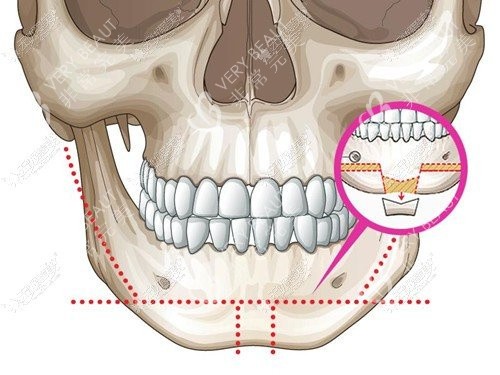

牵张成骨术,是一种内源性骨组织工程技术,通过外科手段将骨骼切开,在切骨线两侧安装特制的牵张器,经过一定的延迟期后,缓慢牵张切骨间隙,使间隙不断增宽,并激发机体组织再生的潜力,在牵张间隙内不断形成新生骨组织。同时,该技术还能使骨骼周围的肌肉、神经、血管、皮肤等软组织同期延长,从而达到延长骨骼、改善形态的目的。

颅面畸形矫正:如小下颌畸形(mandibular micrognathia)、半侧颜面发育不全综合症(hemifacial microsomia)以及各种颅面畸形综合症,如Nager syndrome、Pierre-Robin syndrome、Crouzon syndrome、Treacher-Collins syndrome、Craniofacial synostosis等。

腭裂术后修复:在口腔整形领域,牵张成骨术也被广泛应用于腭裂术后修复,以改善患者的咀嚼功能和面部美观。